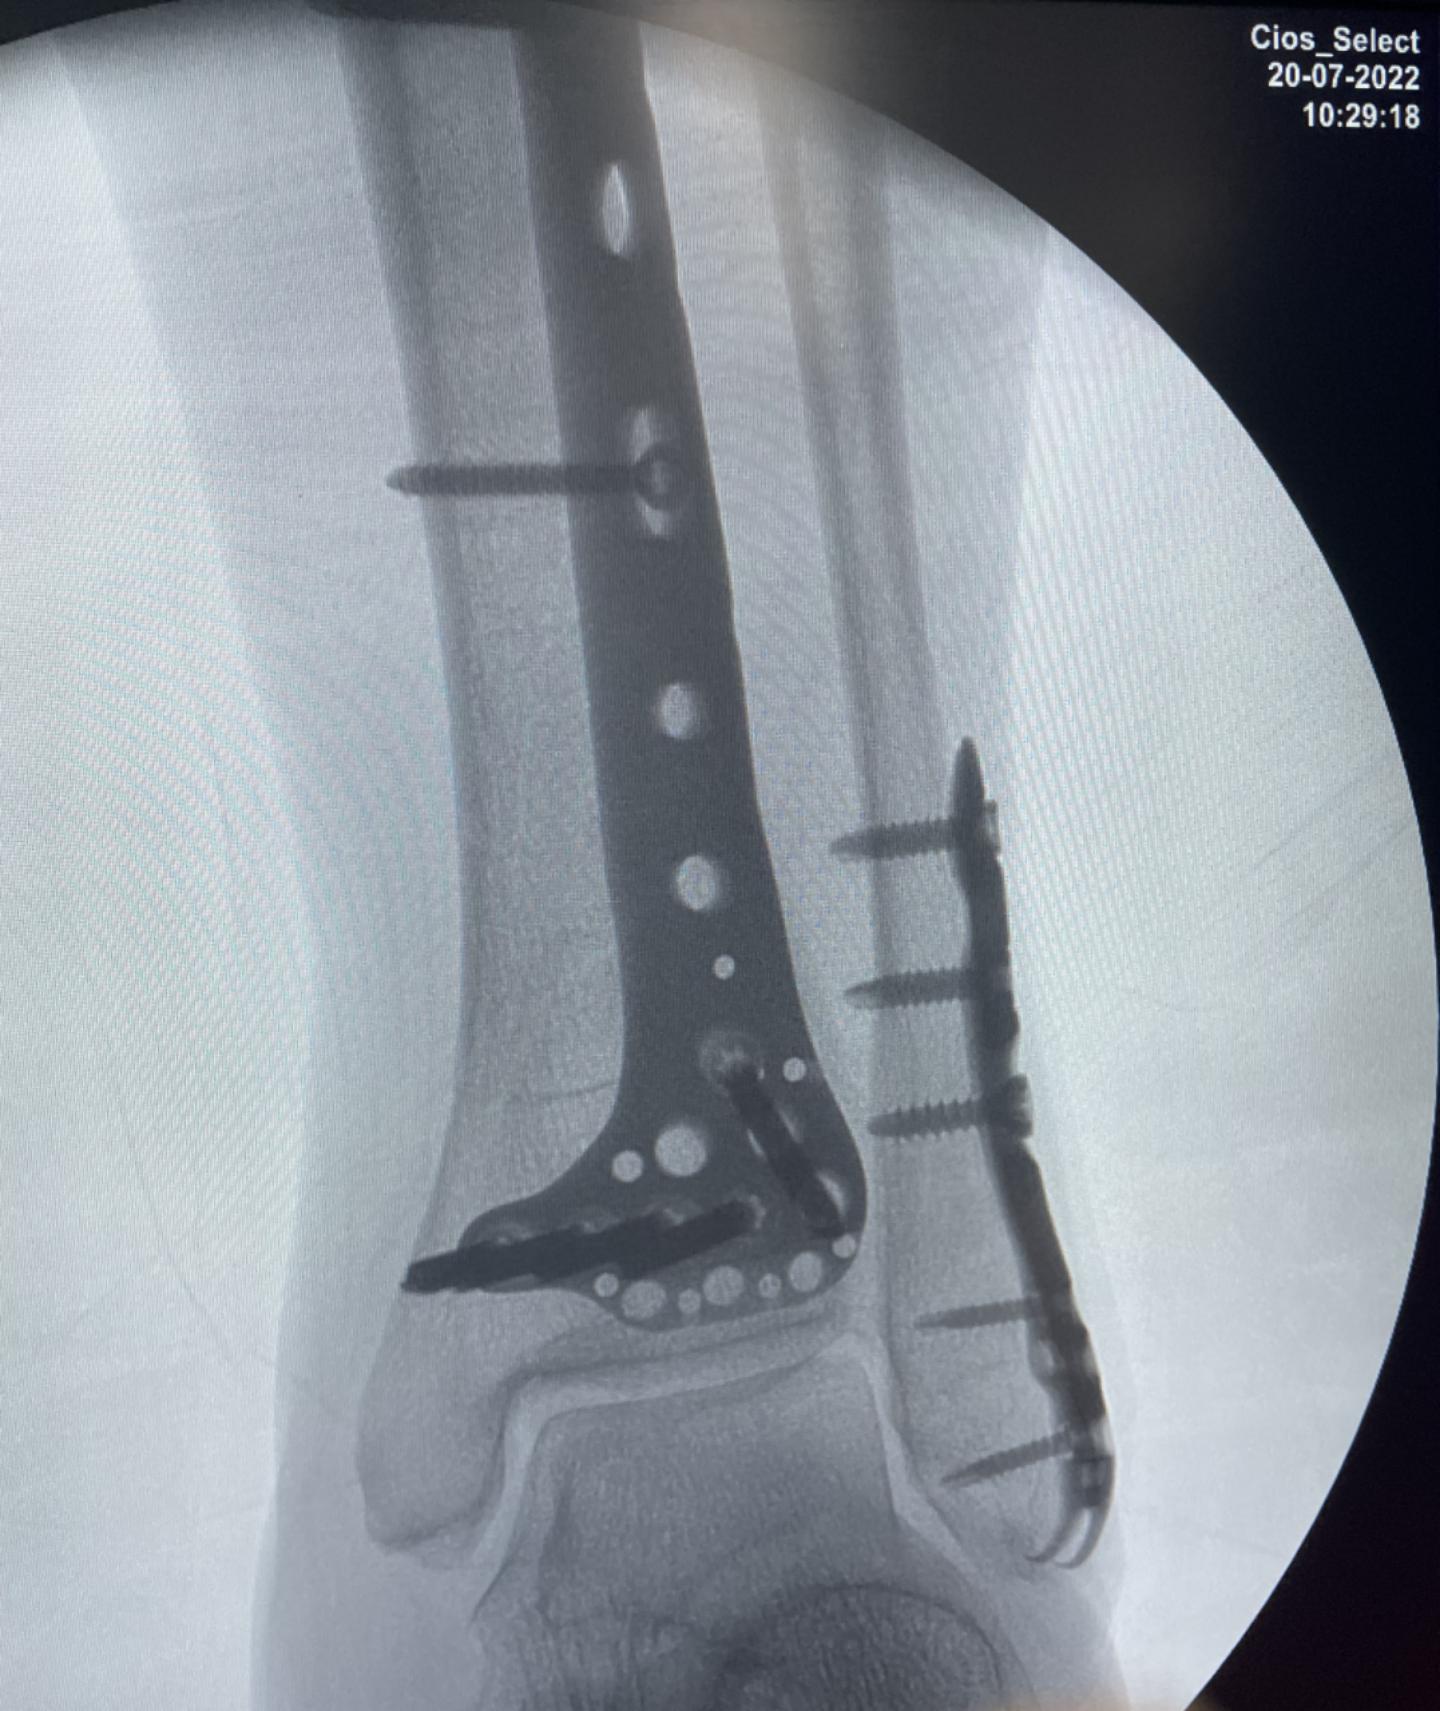

在确定王大娘左小腿软组织肿胀消退,局部擦伤可见好转的情况下,给王大娘进行可进行了左侧胫骨远端骨折闭合复位内固定手术,和左侧腓骨下段骨折闭合复位内固定手术,手术过程很顺利,两处骨折,两个切口,仅用时45分钟。术后继续给王女士冰敷,以防止局部软组织肿胀的进一步加重。

之后,术后复查时左小腿CT结果显示:左侧胫、腓骨骨折端复位良好,内固定位置良好。患者恢复得也很好,在术后第3天进行了左膝踝关节的主动屈伸功能活动,以预防后期的关节僵硬。